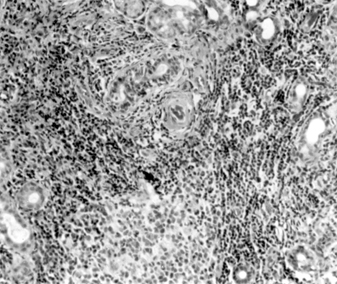

The diagnosis is confirmed by demonstrating lymphocytic and plasma cell infiltration of the accessory salivary glands in a labial biopsy obtained by means of a simple surgical procedure (Figure 5-15).

Figure 5-15

Figure 5-15: Mononuclear infiltration of the accessory salivary glands of a patient with Sjögren's syndrome. (Courtesy of K Tabbara.)

Treatment should be directed toward preserving and replacing the tear film with artificial tears, with obliteration of the puncta, and with side shields, moisture chambers, and Buller shields. As a rule, the simpler measures should be tried first.